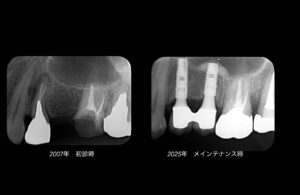

2010年に骨補填剤を用いて上顎洞底を挙上、インプラントを埋入。15年経過するも安定している。

左下第2大臼歯も2010年歯根破折。インプラント埋入後15年経過するが特に問題は起きていない。